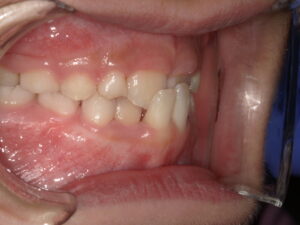

After

| 治療期間・回数 | 8ヶ月。11回。 |

| 治療方法 | リンガルアーチによる前歯の被害改善。 |

| 費用 | 55000円 |

今回は骨格的には問題なく、前歯2本の歯の生える向きがずれてしまっているだけなので リンガルアーチにて上の前歯を前に押し出してあげます。

装置が変形したり、壊れたりして治療期間が長引いてびいてしまいましたが だいたい3~4か月くらいで治ります。